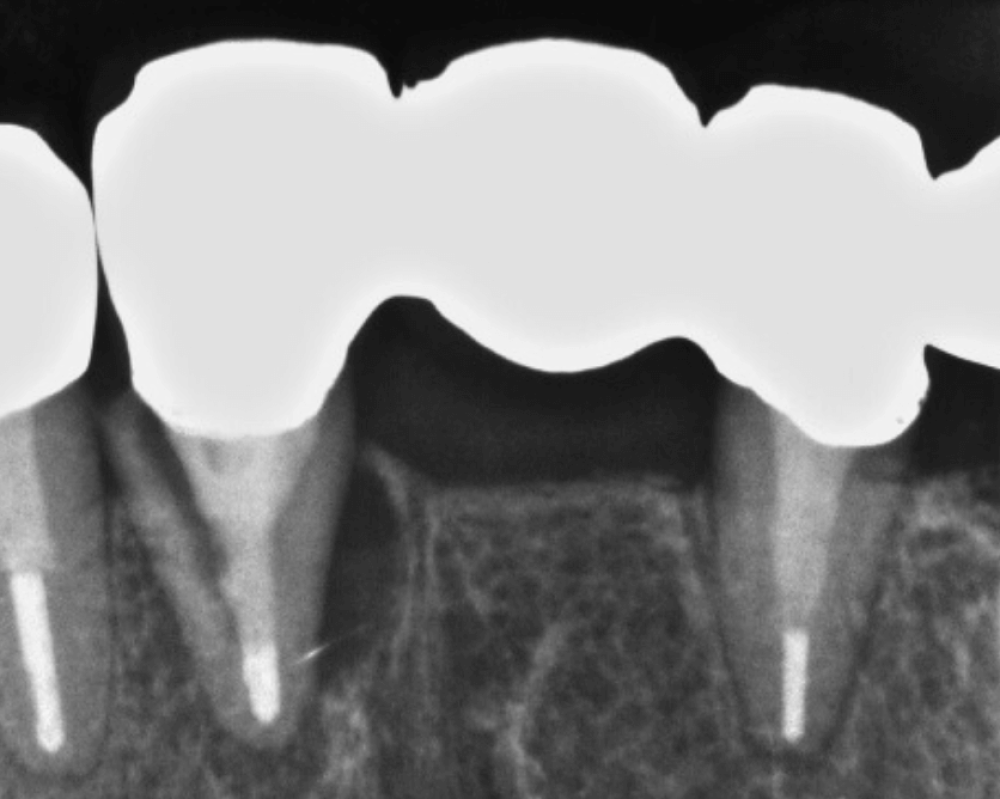

② ブリッジの特徴

✔ 連結構造で安定性あり

✕ 両隣の歯を削る必要

土台となっている両隣の歯に負担がかかるため、将来的に歯根が折れやすい。